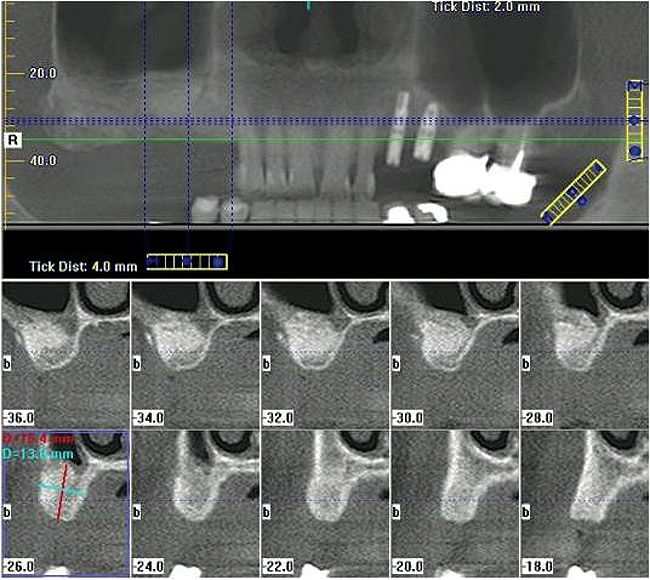

Figure  5  A cone-beam scan was performed prior to the lateral window sinus lift.

Figure 5